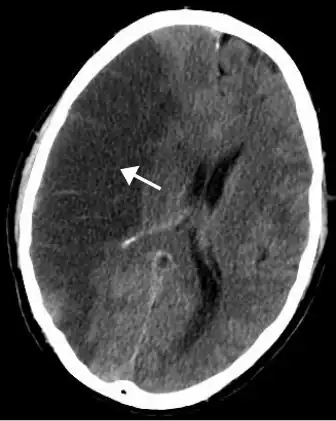

CT scan of the brain showing a massive, prior right-sided ischemic stroke from blockage of an artery. Changes on a CT may not be visible early on.[1]

The most significant risk factor for stroke is high blood pressure.[7] Other risk factors include high blood cholesterol, tobacco smoking, obesity, diabetes mellitus, a previous TIA, end-stage kidney disease, and atrial fibrillation.[2][7][8] Ischemic stroke is typically caused by blockage of a blood vessel, though there are also less common causes.[13][14][15] Hemorrhagic stroke is caused by either bleeding directly into the brain or into the space between the brain's membranes.[13][16] Bleeding may occur due to a ruptured brain aneurysm.[13] Diagnosis is typically based on a physical exam and supported by medical imaging such as a CT scan or MRI scan.[9] A CT scan can rule out bleeding, but may not necessarily rule out ischemia, which early on typically does not show up on a CT scan.[10] Other tests such as an electrocardiogram (ECG) and blood tests are done to determine risk factors and possible causes.[9] Low blood sugar may cause similar symptoms.[9]